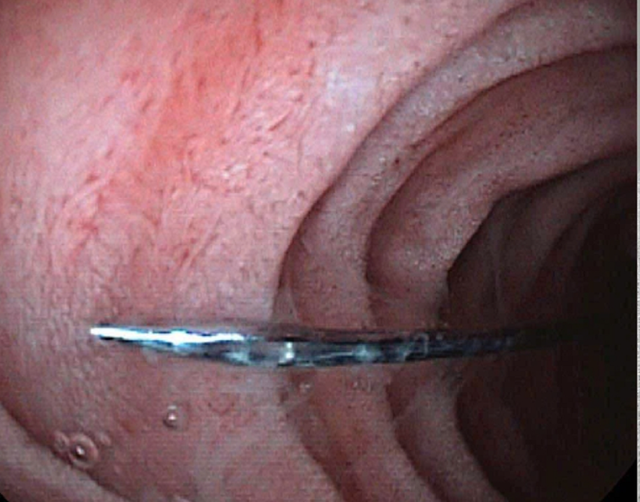

Kim may trong đường tiêu hóa của trẻ. Ảnh BVCC.

Tại bệnh viện, bệnh nhi tỉnh táo, sinh hiệu ổn định. Hình ảnh X-quang cho thấy một dị vật cản quang dạng kim may dài khoảng 4 cm nằm ở đoạn trên ổ bụng. Được biết, bé có tiền sử chậm phát triển tâm thần được chẩn đoán từ 2 năm trước.

Khi đưa ống soi mềm qua đường miệng vào ống tiêu hóa trên, ghi nhận dị vật kim may nằm ở vị trí D2 tá tràng, kèm xước nhẹ niêm mạc hành tá tràng. Dị vật sau đó đã được các bác sĩ gắp ra an toàn. Hiện sức khỏe bé đã ổn định và đang hồi phục tốt.